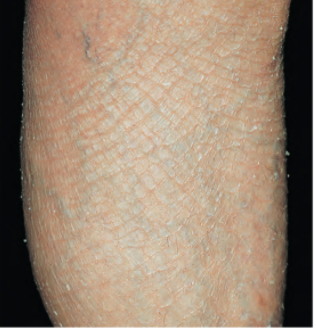

• “Fish” refers to fish like scales

• Mild-moderate scaling on the extensor extremities

Ichthyosis vulgaris

• Filaggrin deficiency = impaired formation of cornified keratinocytes

• increases your loss of epidermal water

• much more likely to have inflammatory rxn when exposed to irritants or allergens

• diagnosis:

• clinical diagnosis

• tx:

• Emollients or keratolytic agents